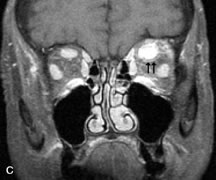

Breast carcinoma metastatic to the orbit has been demonstrated to be hypointense to the surrounding orbital fat on T1-weighted studies and hyperintense on T2-weighted images and has an affinity to the extraocular muscles (Fig. 20).50,64 The MRI characteristics of prostate carcinoma metastatic to the orbit have been described as involving the greater and lesser wing of the sphenoid, orbital roof, and optic canal. Diffuse bone hypertrophy with isointense or slightly hyperintense tissue on T1-weighted images represents the osteoblastic carcinomatous bone infiltration. Contrast enhancement is variable on T1-weighted and fat-suppressed images.65

Fig. 20. A. T1-weighted MR scan demonstrates nodular enlargement of both medial rectus muscles (arrows). B. T1-weighted fat-suppressed contrast-enhanced scan confirms the presence of small metnstatic deposits within the muscles (open arrows).